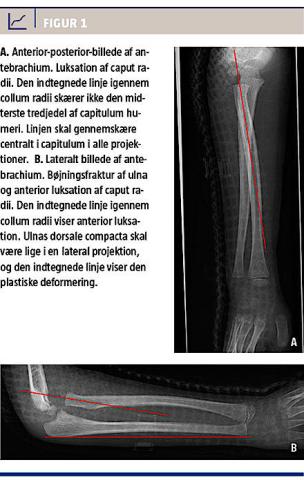

En seksårig, rask dreng faldt og slog armen, hvorfor forældrene søgte den lokale skadestue. Her blev det vurderet, at et røntgenbillede i anterior-posterior (AP) og lateral projektion var indiceret, men dog kun af albueleddet. Billederne blev fortolket som værende normale, og drengen blev sendt hjem igen til konservativ behandling. Efter at han i to uger havde haft nedsat ekstension og fleksion i albueleddet kombineret med nedsat supination i håndleddet, valgte egen læge at foranledige en ny røntgenundersøgelse af albueleddet, hvilket resulterede i fundet af en anterior luksation af caput radii. Patienten blev genhenvist til ortopædkirurgisk afdeling på det lokale sygehus, som henviste til Ortopædkirurgisk Afdeling, Aarhus Universitetshospital. Røntgenundersøgelsen blev her suppleret med AP-projektion og lateral projektion af den totale underarm (Figur 1). Disse billeder viser den plastiske deformering af ulna.

MF er relativt simpel at diagnosticere, hvis man er opmærksom på den beskrevne patologi. Ud fra AP-optagelsen alene kan diagnosen ikke stilles [3], hvorfor en lateral projektion, som inkluderer hele antebrachium, er indiceret. Ved MF hos børn ses der ofte ingen frakturlinje (Figur 1), og røntgenoptagelser af albuen i to planer eksklusive antebrachium kan derfor let misfortolkes som værende normale, trods tilstedeværelsen af MF. Røntgenoptagelse i to planer, hvor hele antebrachium er inkluderet, visualiserer luksationen af caput radii samt den ulnare bøjningsfraktur og er derfor essentiel for at stille diagnosen [3]. Hvis man indtegner to hjælpelinjer på røntgenbillederne, kan diagnosen nemt stilles. Indtegnes en længdeakse midt i collum radii, skal denne gennemskære den midterste tredjedel af capitulum humeri i alle projektioner. Endvidere skal ulnas dorsale compacta på en sand lateral optagelse være lige (Figur 1B). Diagnosticeres tilstanden ikke, vil barnet kunne opleve smerte, instabilitet, deformitet (cubitus valgus) samt tab af kraft og bevægelighed i albueleddet i sit voksenliv [4].